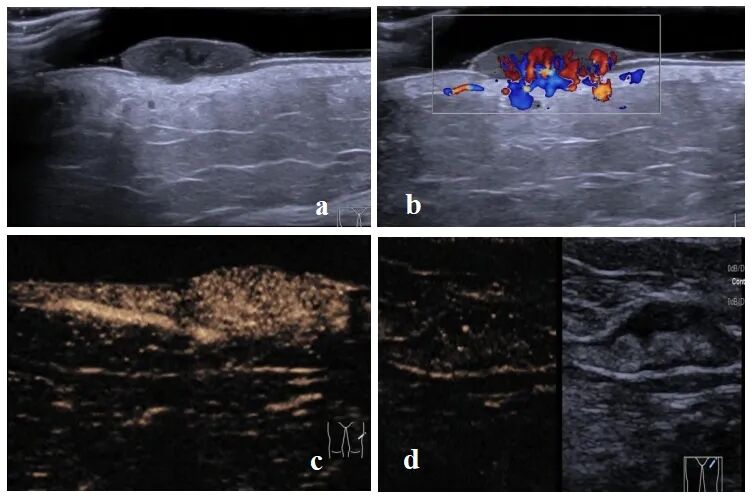

a 真皮层黑色素瘤二维声像图 ;b真皮层黑色素瘤彩色多普勒声像图 ;c真皮层黑色素瘤超声造影声像图 ;d通过超声造影定位前哨淋巴结。